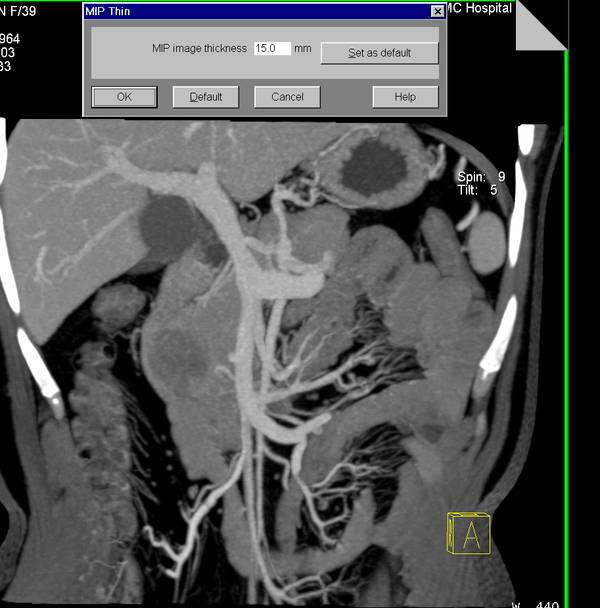

2、MIP(最大密度投影)将三维数据向某方向进行投影,取投影线经过的所有体素中最大的一个体素值,作为结果图像的像素值。适用于高密度组织结构和病灶的显示,如CTA、血管壁钙化、气管通畅情况等。它体现了密度信息,但不能测量CT值。